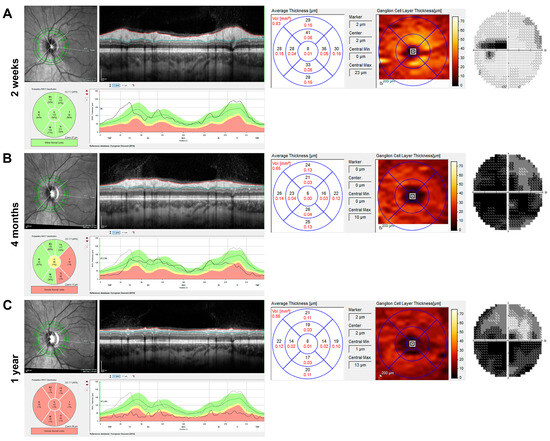

Among the LHON patients, two patients received two OCT scans during the first year, two received three scans, two received four scans, and one patient each received five, six, and seven scans, respectively. Among the optic neuritis patients, nineteen patients received two scans, and one patient received three scans. The normally doughnut-shaped GCL showed a significant reduction in thickness soon after vision loss in LHON patients (Figure 2 shows the OCT and visual field of a representative patient two weeks, four months, and one year after vision loss), whereas the RNFL appeared preserved or supernormal in the first weeks (2A) and continuously atrophied during the first year.

Figure 2. Imaging and visual field of the left eye of a 25-year-old Leber hereditary optic neuropathy (LHON) patient with m.11778G→A mutation during the first year after the onset of symptoms. Analysis of retinal nerve fibre layer (RNFL) and macular ganglion cell layer thickness (GCLT) by spectral-domain optical coherence tomography (SD-OCT, Heidelberg Engineering, Heidelberg, Germany) and Humphrey visual field (30-2, Analyser 3, Zeiss, Jena, Germany) are shown from left to right for three time points. (A) Two weeks after symptom onset, there was subtle swelling of the peripapillary RNFL, but already reduced GCLT in all sectors, particularly in the nasal foveal region. Centrocecal scotoma was present, and the visual acuity was 0.80 log MAR at this time. (B) At four months, the RNFL was partially reduced, especially in the temporal region, but there were hardly any ganglion cells visible in the colour image of the GCLT analysis. Almost complete loss of the central visual field was observed over the months. (C) One year after the onset of symptoms, circular atrophy of the RNFL and further reduction in the GCLT were observed with visual field depression, showing enlarged fenestration in the upper visual field.